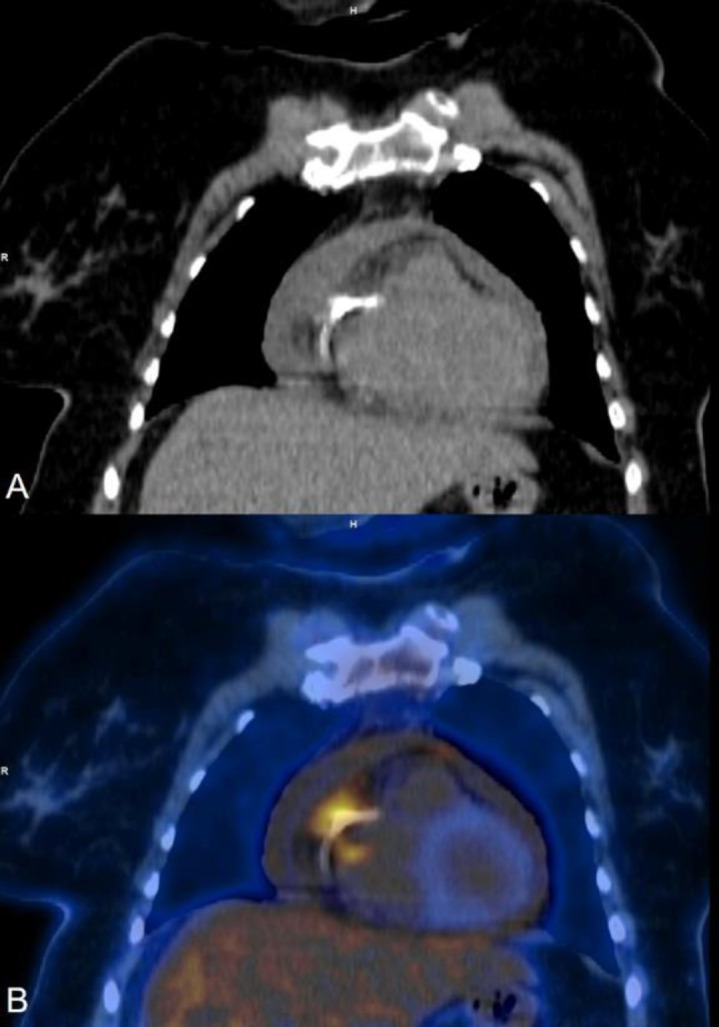

随着介入心脏病学手术数量的增加,心脏设备感染(包括起搏器、人工瓣膜、冠状动脉和主动脉支架)的数量也在增加。这些感染会导致严重的发病率,如果处理不及时甚至会导致死亡。如果临床上怀疑有心脏装置感染,第一线影像检查方法是经胸超声心动图,经食道超声心动图也可用于特定病例。心脏设备感染的确诊大多需要借助血液或脓液培养。尽管超声心动图是一种非常有效的心脏评估技术,但它无法区分感染与血栓或纤维化。随着正电子发射计算机断层扫描(PET CT)机在全球范围内的普及,18F-FDG PET CT 在感染成像中的应用越来越受到重视,尤其是在心脏设备感染方面。最近的大多数研究表明,18F-FDG PET CT 具有良好的诊断准确性,许多最新的诊断和管理指南都承认了它的作用,尤其是在诊断不明确的病例中。我们介绍了六个这样的病例,在这些病例中,18F-FDG PET CT 为疑似心脏设备感染患者的诊断、确诊感染的存在、划定感染范围、治疗反应,有时甚至帮助做出适当的治疗决策提供了有价值的信息。

With the increasing number of interventional cardiology procedures, the number of cardiac device infections (including pacemakers, prosthetic valves, coronary and aortic stents) have also increased. These infections can cause significant morbidity and can even lead to mortality if not managed promptly. If suspected clinically the first-line imaging modality is Trans-Thoracic Echocardiography, while Transesophageal Echocardiography is also used in selected cases. The confirmation of a cardiac device infection is mostly done with the help of blood or pus culture. Even though Echocardiography is a very efficient technique for the evaluation of the heart, it cannot differentiate infection from thrombus or fibrosis. With the increasing availability of Positron Emission Tomography CT (PET CT) machines worldwide, the use of 18F-FDG PET CT for infection imaging has gained traction, especially for cardiac device infection. Most of the recent studies show a good diagnostic accuracy of 18F-FDG PET CT with many of the recent diagnostic and management guidelines now acknowledging its role, especially in equivocal cases. We present six such cases where 18F-FDG PET CT provided valuable information either for diagnosis, confirming the presence of infection, delineating extent, therapy response or sometimes even helping appropriate treatment decision making in patients with suspected cardiac device infection.